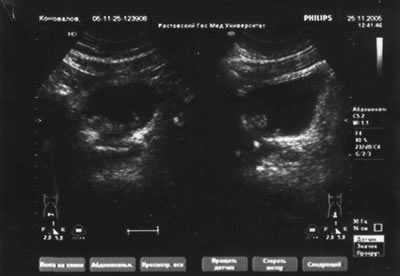

УЗИ мочевой системы – гидронефроза нет, объем мочевого пузыря 300 см3, многофокусный t-r

УЗИ мочевой системы

УЗИ мочевой системы. Рак мочевого пузыря.